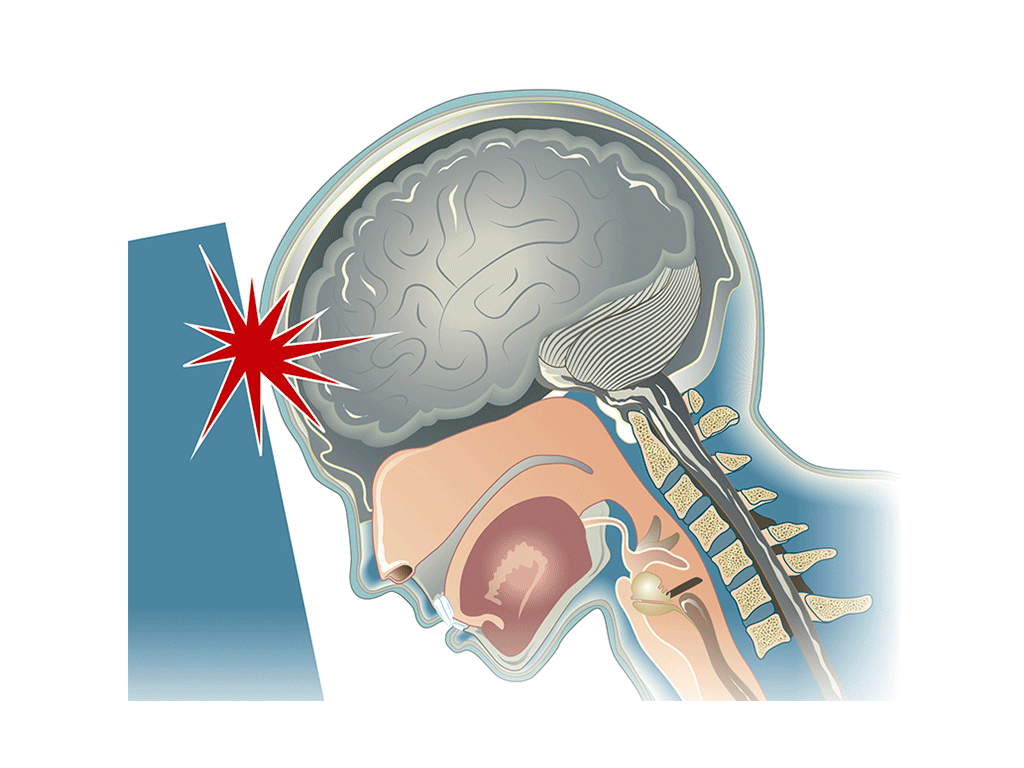

Head

Concussion